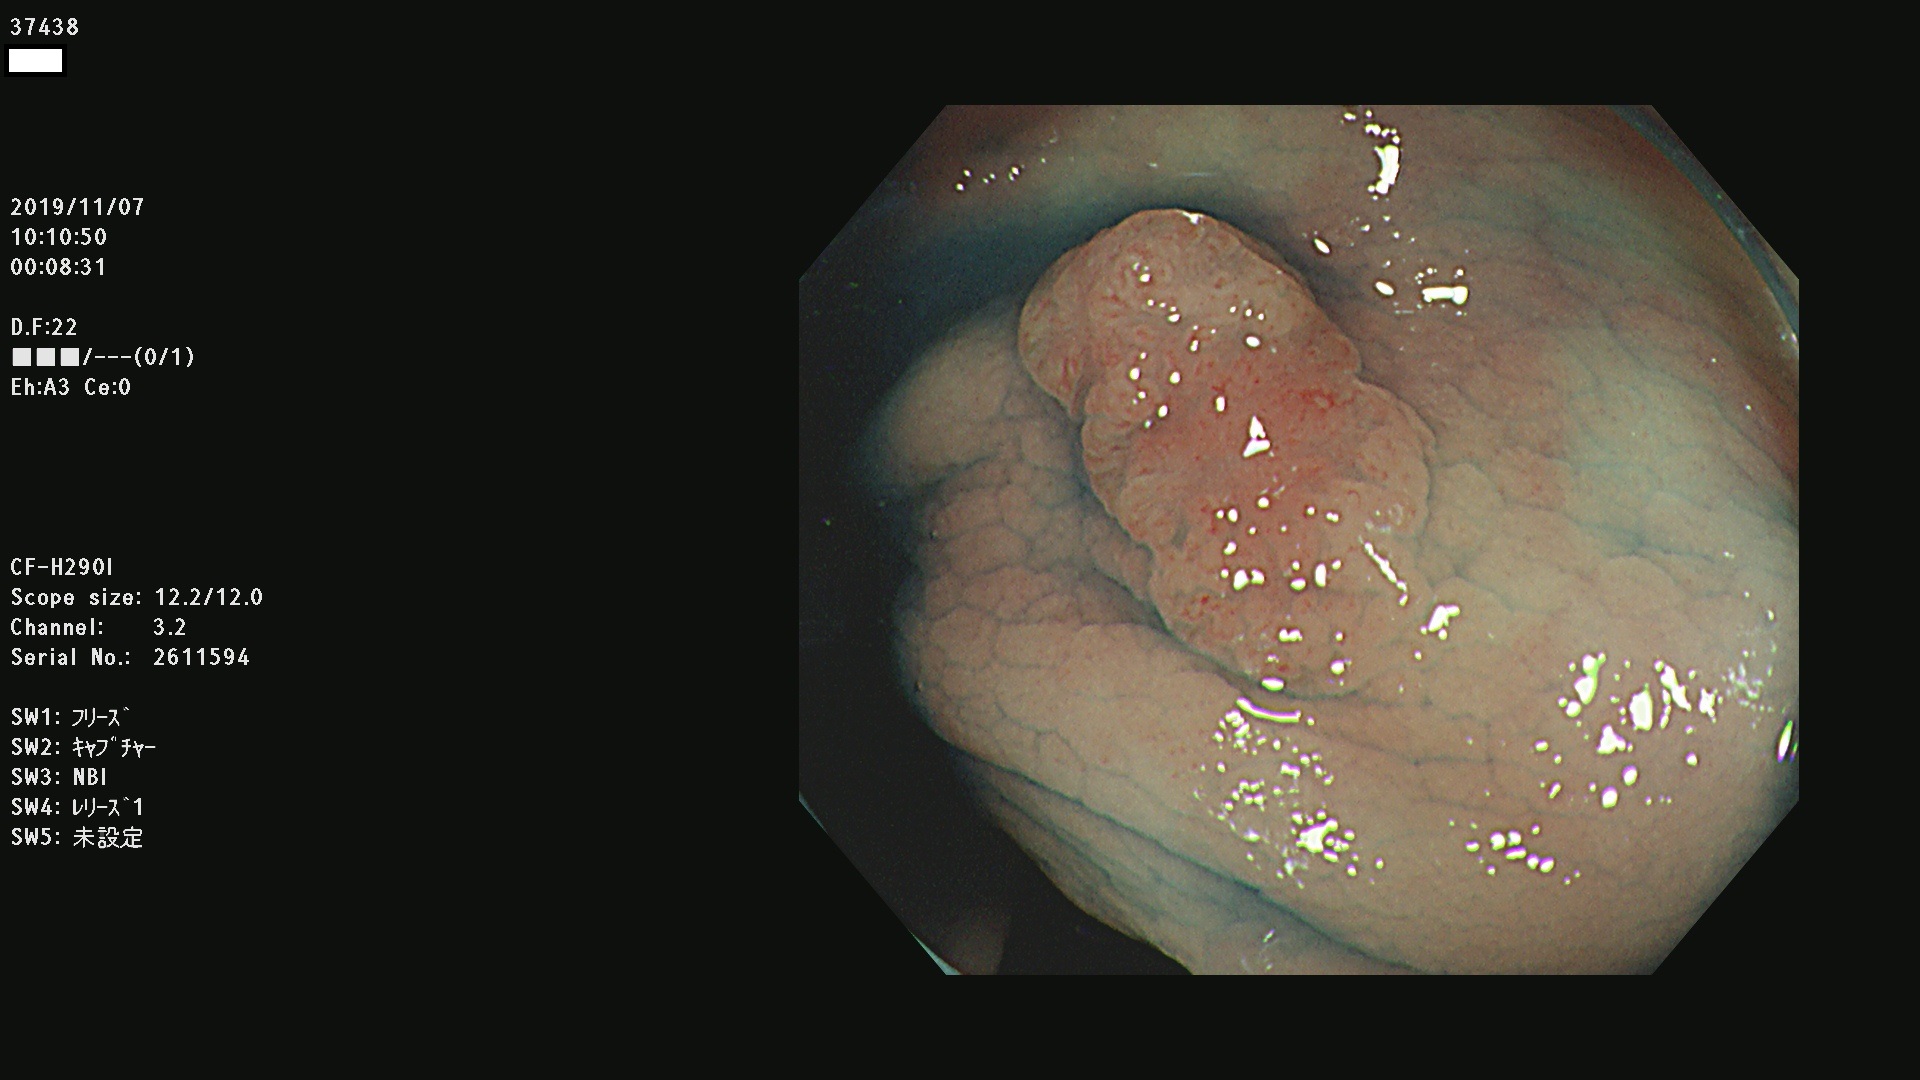

37400(SSAPのみ) 37401 37403 37404 37405 37406 37407 37408 37410 37411 37412 37413 37415 37416 37417 37420 37423 37424 37425 37426 37428 37430(SSAPのみ) 37432 37433 37434 37435 37436 37437 37438 37439 37440 37442 37443 37444 37447 37448 37449 37450 37451 37452 37455 37456 37457 37458 37459 37460 37461 37462 37464 37467 37468 37469 37470(SSAPのみ) 37471 37472 37474 37476(SSAPのみ) 37477 37478 37480 37481 37482 37483 37485 37486 37487 37488 37489 37490 37491 37492 37493 37494 37497 37499

発見困難で危険性の高い平坦型病変(上記100名より抽出)